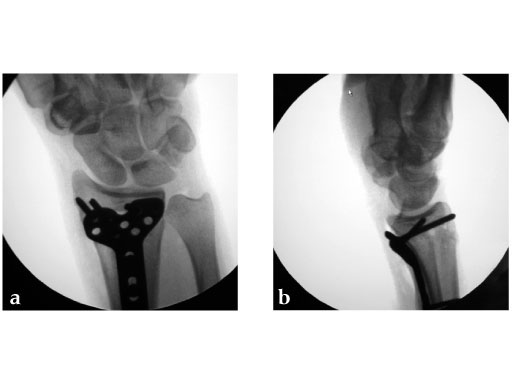

28-year-old woman.

Fig 3ab: X-rays postoperative.

Case provided by Jesse Jupiter, Boston.